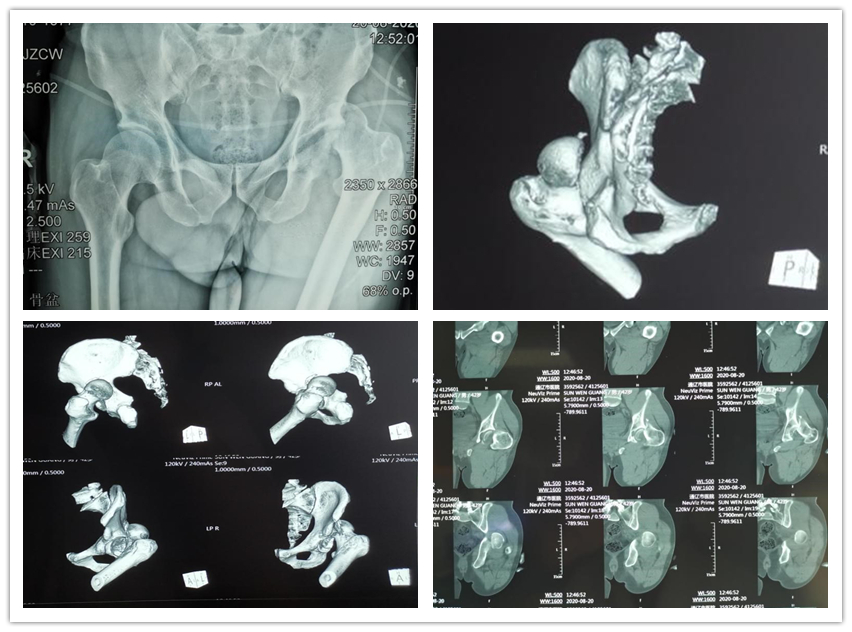

.jpg)

切口以大转子为中心,自髂后上棘外下5-6cm处经大转子至大腿外侧中线向下做一长约12-16cm切口,确认臀中肌及股外侧肌位于大转子上的附丽点,平行股骨失状面截骨,一般截骨厚度为1.5-2cm,上下保留臀中肌及股外侧肌附丽点,因此,亦称为双腹截骨,也称滑动截骨。此时可以将骨块拉向前方,近端剥离位于臀中肌深面的臀小肌,即可暴露髋臼顶部及前方关节囊。

术中可以充分显露脱位的股骨头及其残留在髋臼内的前内侧骨块,同时该患髋臼后壁带有关节盂唇的撕脱性损伤。首先将附着于股骨头前内侧骨块的圆韧带切除,取出骨块后解剖复位在股骨头上,利用1.5mm克氏针临时固定,并选用3枚适宜长度的Herbert钉固定。复位髋关节,将后壁骨块依照股骨头为标准复位,选用铆钉及3.5mm螺钉固定。最后将大粗隆截骨块复位,采用2枚4.5mm拉力螺钉固定。术中透视满意。手术顺利结束,用时约1小时30分,出血量约300ml。病人清醒回普通病房。